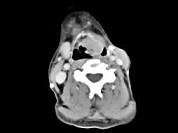

男,53岁,咽部不适半年余,近2个月感咽部疼痛,声嘶,CT如图所示,应诊断为 ( )

答案: D